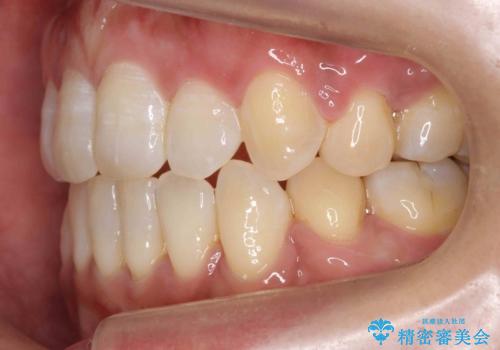

右上以外の3本を抜歯しきちんと並べました。

矯正に年齢は関係ありません、あきらめずにまずはご相談を!

前歯も引っ込み、口が閉じやすくなりました。